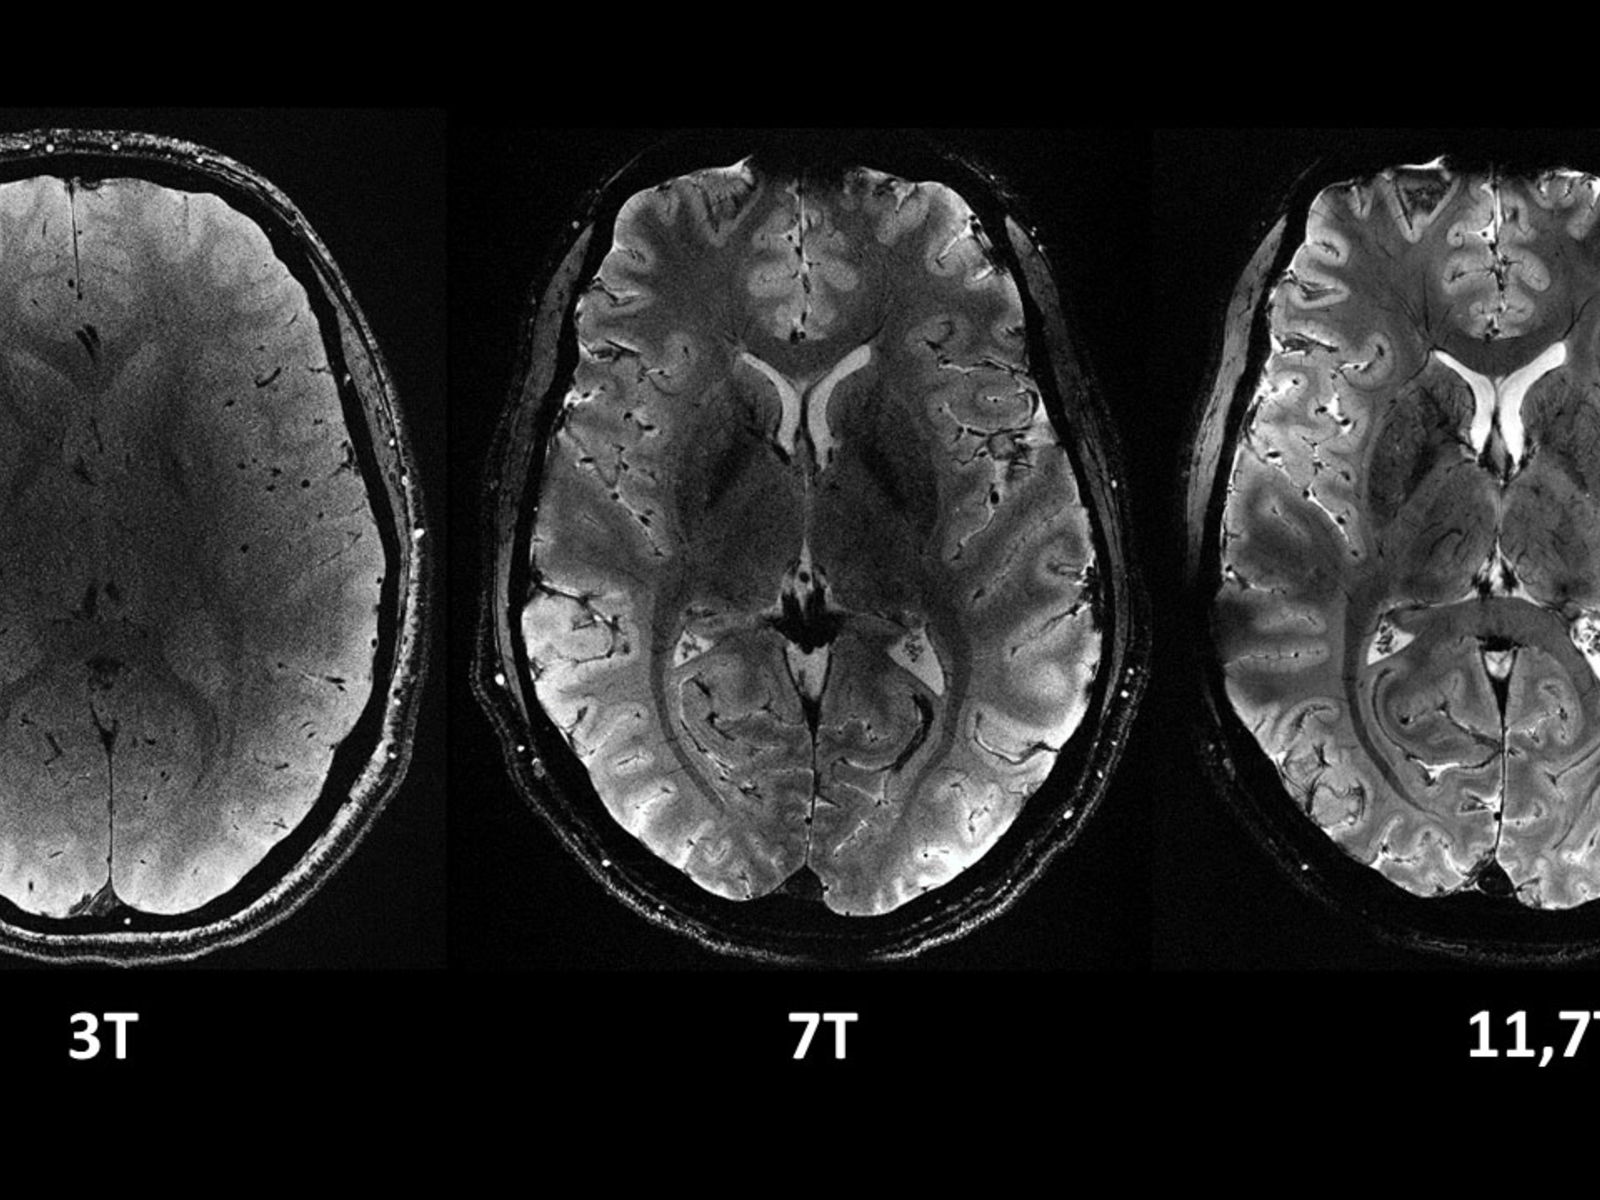

Valeria Herdea a menţionat că un examen RMN nu se face pentru orice şi doar la indicaţia medicului.

”Ierahizarea se face de către medicul curant care este managerul de caz. Dânsul îşi asumă ce face cu pacientul unde îl trimite şi de ce, sigur respectându-i independenţa profesională. Nu se pune problema. Un medic independent profesional, decide cu expertiza lui şi cu capacităţile lui ce trebuie să facă cel mai bine pentru pacient şi îl rezolvă la nivelul lui sau îl trimite. Medicina de familie rezolvă aproximativ 75-80% din lucruri. Se duce şi spre ambulator, unde la fel poate fi investigat şi tratat corect. Nu se rezolvă şi este urgent se pleacă în spital. Nu merg la spital să fac RMN pentru orice, pentru că atunci nu vor fi fonduri suficiente. Avem investigaţii CT în fiecare spital din ţara asta. Nu cred că există foarte multe spitale care să nu permită accesul pentru acest serviciu. Sigur cu toţii ne dorim investigaţii de top, dar trebuie văzut dacă e nevoie de ele. Nu doar să cerem în plus”, a mai afirmat Valeria Herdea.